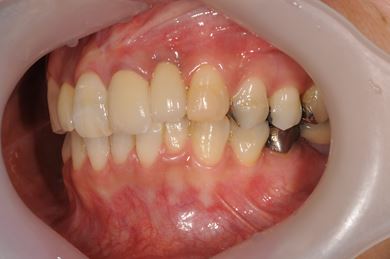

骨再生インプラント治療+セラミック治療

| 治療方針 | 骨再生法により、インプラント治療を可能にする。 | ||||||||||||||||||||||||||||||||

| 治療内容 | インプラント1本、メタルボンドセラミッククラウン2本、GBR | ||||||||||||||||||||||||||||||||